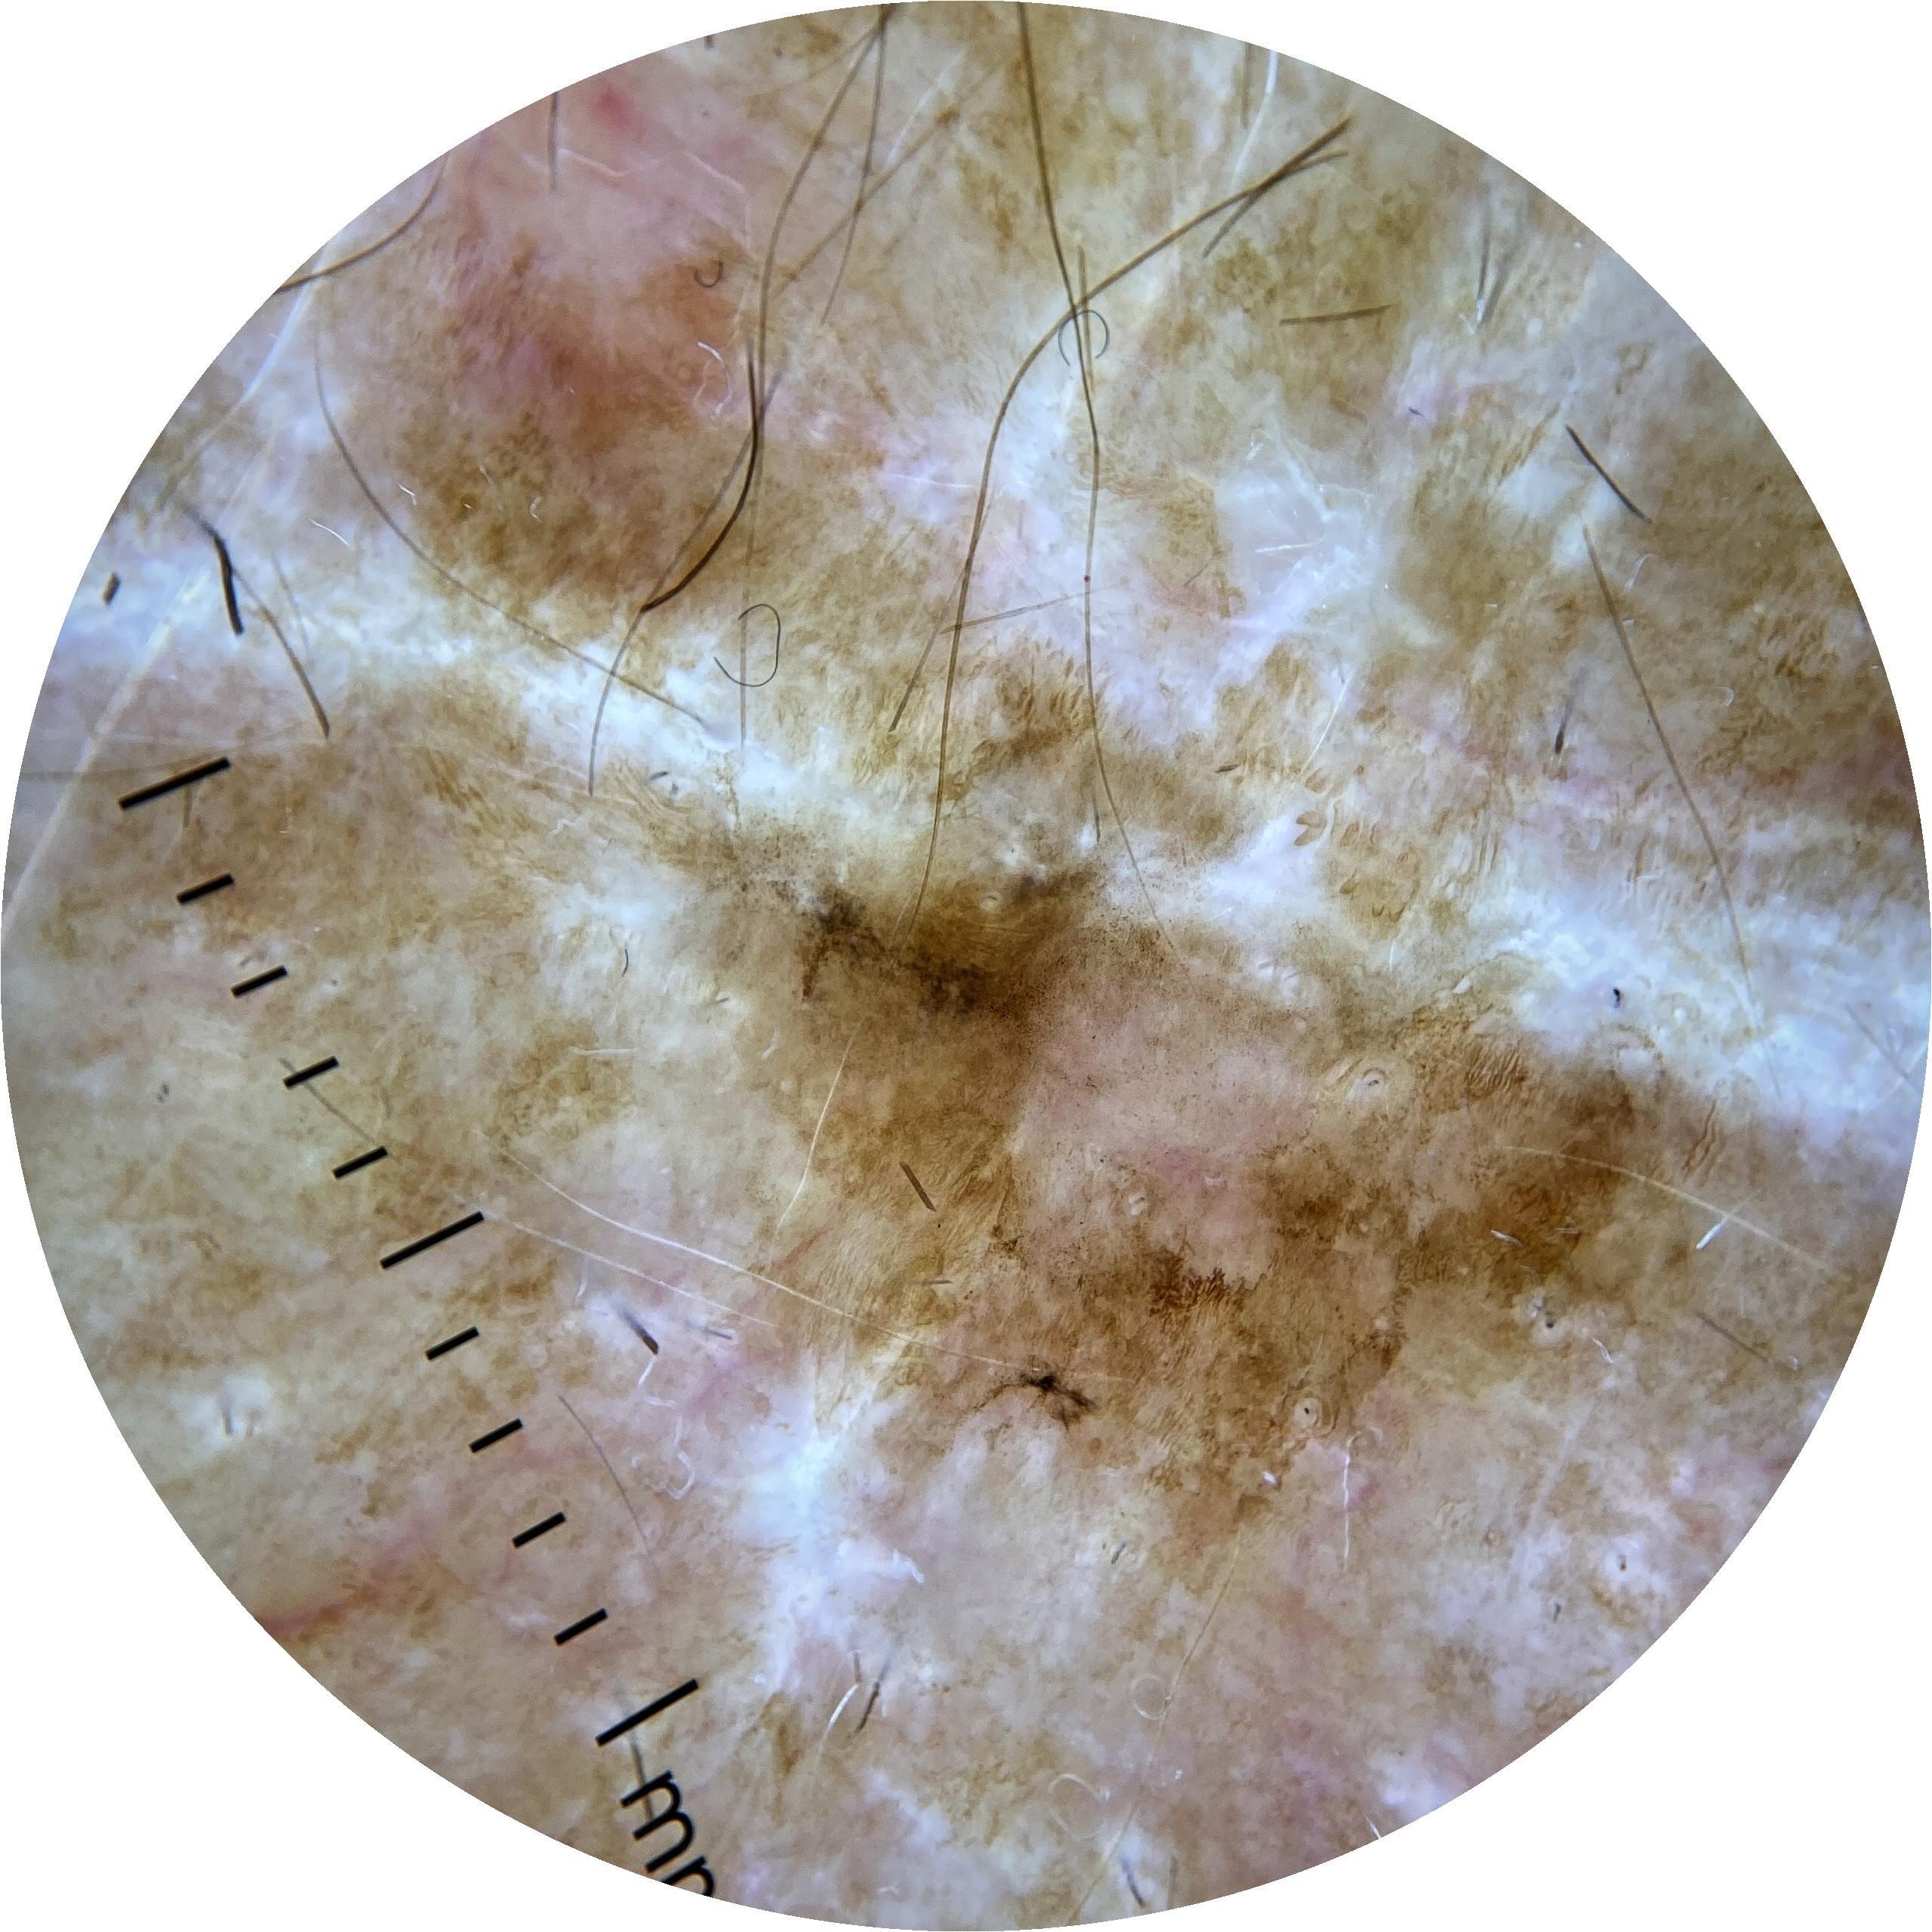

ISIC_7521238

MEL-SELF Trial, https://www.sydney.edu.au/medicine-health/our-research/research-centres/melself-project.html

acquisition_day 258

age_approx 80

anatom_site_1 Upper extremity

anatom_site_general upper extremity

diagnosis_1 Benign

diagnosis_confirm_type single image expert consensus

fitzpatrick_skin_type I

image_type dermoscopic

personal_hx_mm True

sex male